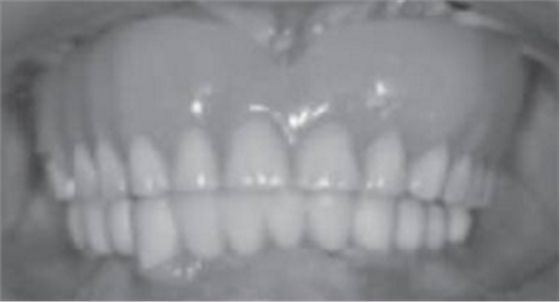

圖17 臨時義齒面照

圖18 戴臨時義齒微笑照